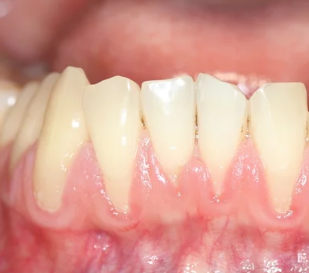

4. 잇몸이 내려가고 치아가 길어 보인다 – 잇몸 퇴축 현상

잇몸뼈가 녹아내리면, 잇몸이 치아뿌리 쪽으로 물러나면서 치아가 길어 보이는 현상이 나타납니다.

- 거울로 보면 치아가 평소보다 길게 보임

- 잇몸 경계가 울퉁불퉁하고 균일하지 않음

- 찬물 마실 때 시림이 심해짐

▶ 치아가 길어지는 건 단순한 미용 문제가 아닌 치아지지 구조 약화의 증거입니다.

5. 이가 흔들린다 – 이미 진행된 중등도 이상 치주염

정상적인 치아는 손으로 흔들어도 거의 움직이지 않습니다.

하지만 치주염이 심해지면 **치아를 고정하던 잇몸뼈(치조골)**가 파괴되면서 치아가 실제로 흔들리기 시작합니다.